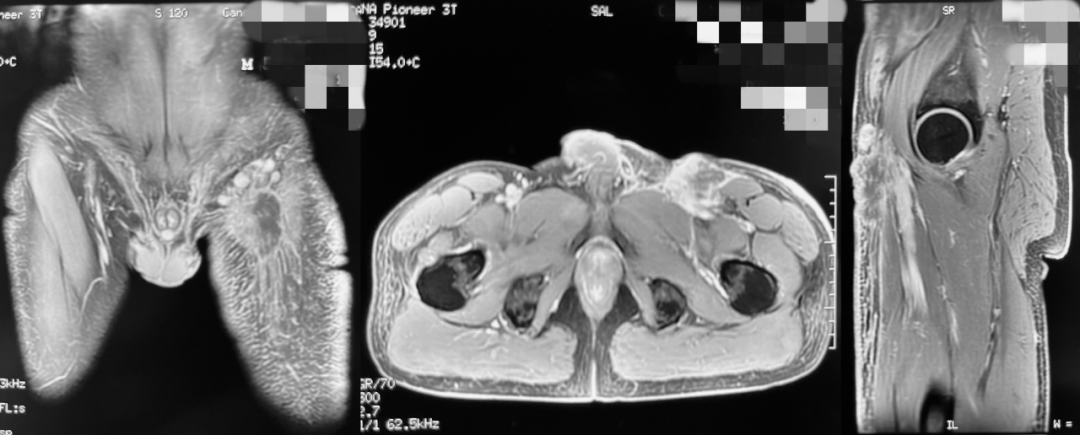

术前MRI检查示腹股沟区肿瘤侵及股三角大血管